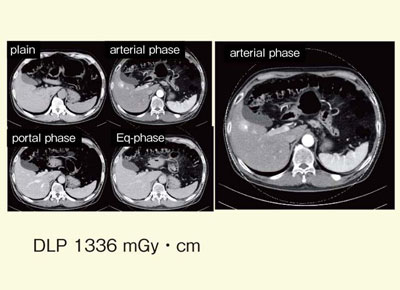

CTを用いた肝臓領域の血流動態解析手法には,多相造影CT,CT perfusion,シネCTHAなどがあるが,いずれも複数回のスキャンを行うため被ばく量が多くなる。したがって,CTを用いた肝血流動態解析には,低被ばくのCTが望まれている。既存の従来機種とDefinition FlashのDEイメージングで撮影した同一患者・同一プロトコールの画像を比較すると,従来機種のDLPは7600 mGy・cm,Definition FlashのDLPは3600 mGy・cmと,明らかにDefinition Flashの方が少なくなっていることが認められる。

図2はAP shuntの症例だが,被ばく量が減少しても病変はしっかり描出されている。また,結腸がん肝転移の症例では,少ない被ばく量にもかかわらず,小さな肝転移の描出能は従来機種と同等であることが認められる(図3)。

![]() 図2 AP shuntの症例(68歳,男性,C型慢性肝炎) |

![]() 図3 結腸がん肝転移の症例(53歳,男性) |